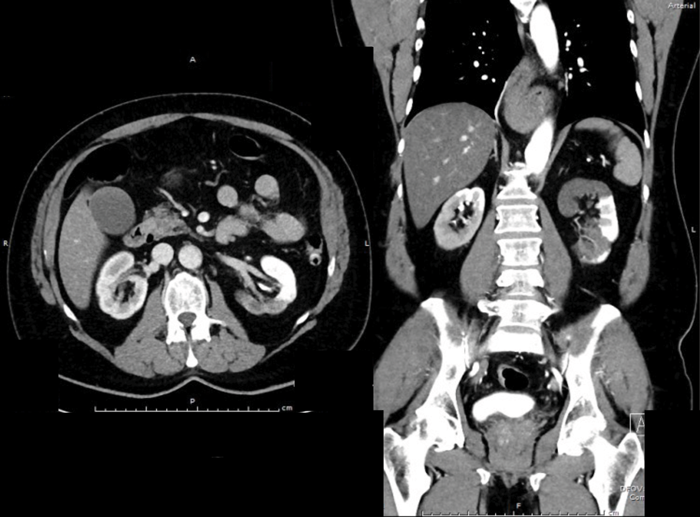

A previously fit and well 65-year-old man presents with acute onset, left loin pain and non-visible haematuria. He underwent a CT KUB suspecting renal stones (no stones seen), therefore he had a subsequent contrast CT scan. These images are shown below:

There is diffusely marked hypo perfusion throughout the right kidney. The left kidney demonstrates an infarction of the posterior and superior segments of the left kidney.

The two main causes of renal infarction are thromboembolic, commonly from a thrombus in the heart or aorta (cardiomyopathy, endocarditis, artificial valve thrombi or AF) and in-situ thrombosis. Less common causes include: hypercoagulable states, sub-therapeutic warfarin dosing, renal artery dissection, aortic dissection (as in this case), trauma, Marfan syndrome, polyarteritis nodosa or idiopathic.